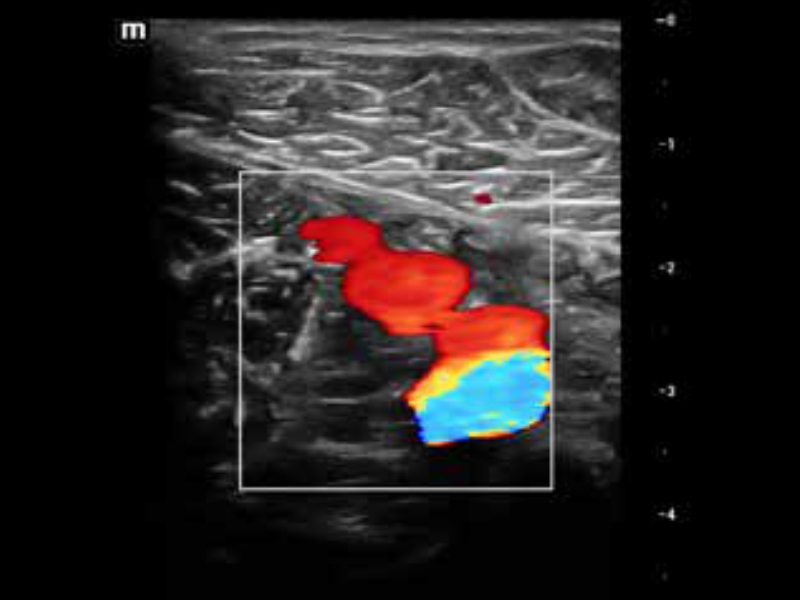

• zeus-fig5-1-2-uk

Perfuzja nerek